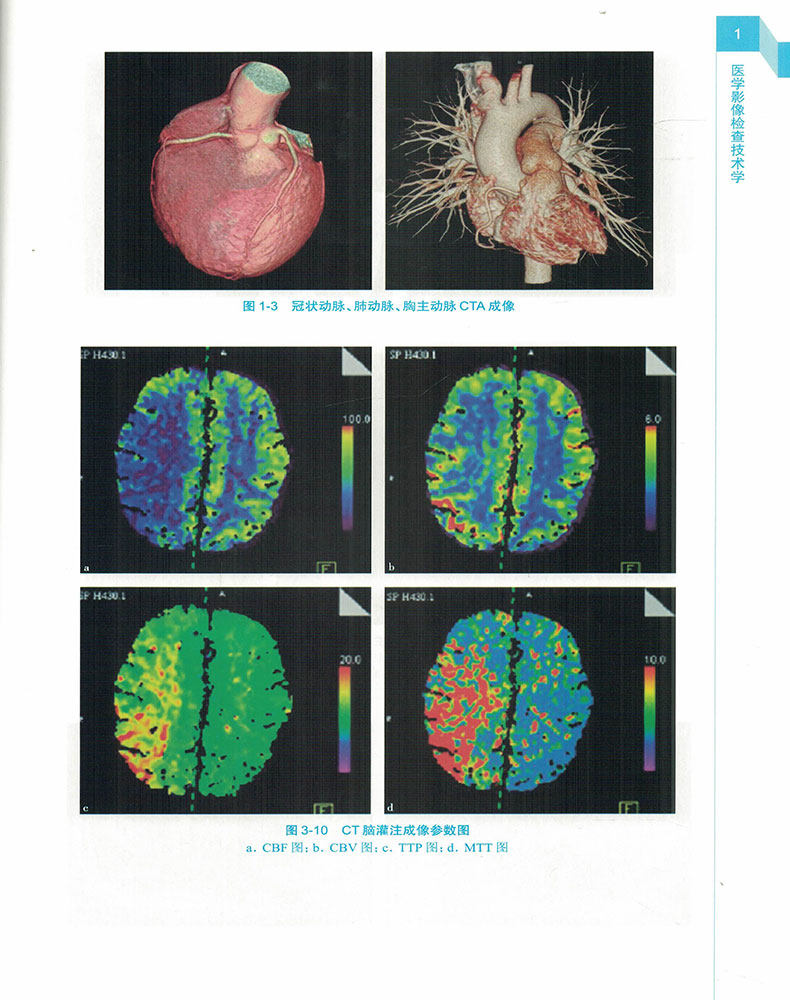

Man Wei 2020 Medical Imaging Inspection Technical School 13 Five Planning Teaching Materials Undergraduate Radiography Technologiestechnician Professional use 9787117229401 People's Health Press Fourth Edition

Technical Studies in Medical Imaging Inspection,Technical Studies in Medical Imaging Inspection